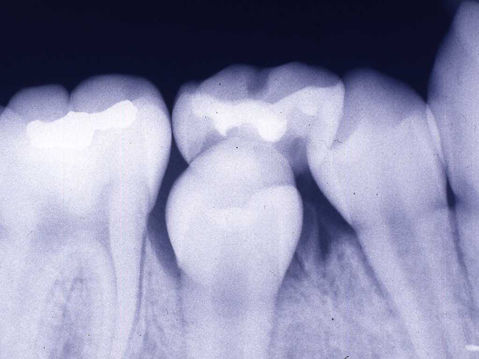

交換期の乳歯でみられる生理的吸収

・歯の内部吸収 (internal resorption) 歯髄内での肉芽組織の限局性増生による歯髄壁象牙質の吸収 吸収部の象牙質では、波状の吸収窩と破歯細胞がみられる